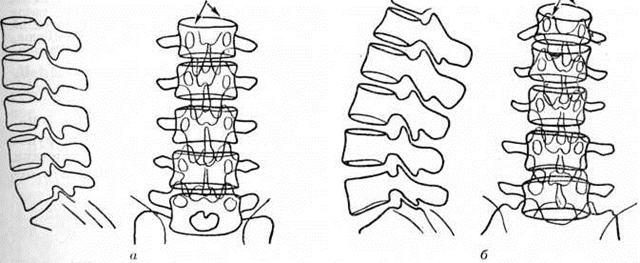

Нечёткое изображение тел позвонков на рентгенограмме в прямой проекции при усиленном Лордоз требует дополнительного снимка в этой же проекции, но при изменённом направлении хода лучей. Для получения чёткого изображения верхних поясничных позвонков центральный пучок рентгеновского излучения центрируют в краниокаудальном направлении, а нижних шейных позвонков — каудокраниальном. Степень фиксированности (или подвижности) Лордоз может быть определена с помощью рентгено-функционального исследования. С этой целью производят снимки позвоночника в боковой проекции при обычном вертикальном положении обследуемого, а затем в состоянии максимального сгибания и разгибания. Объективная характеристика кривизны позвоночника основывается на учёте радиусов дуг, проекционно соединяющих на боковой рентгенограмме аналогичные точки тел позвонков

на их передних или задних поверхностях. Чем меньше радиус кривизны, тем сильнее выражен Лордоз На рентгенограмме в прямой проекции о степени Лордоз можно судить по величине расхождения переднего и заднего края тела I поясничного позвонка (рисунок 6). Иногда при выраженном Лордоз